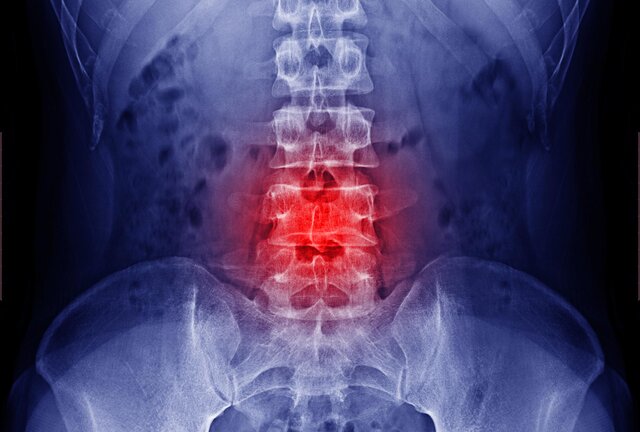

در گزارش پژوهشگران دانشگاه جانز هاپکینز آمده است: سالانه حدود 400 هزار نفر در آمریکا، به خاطر عدم ثبات، درد و یا نقص عملکرد مهرههای ستون فقرات، تحت عمل جراحی قرار میگیرند. در این گونه موارد، درمانهای کمکی باید برای کمک به روند ترمیم استخوان آغاز شوند.

یکی از درمانهای کمکی، تحریک الکتریکی است. در حال حاضر، سه نوع تحریک الکتریکی وجود دارند؛ تحریک جریان مستقیم، تحریک اتصال خازنی و تحریک اتصال القایی.

در بررسی این مقالات مشخص شد که تحریک الکتریکی میتواند در تقویت جوش خوردن مهرهها موثر باشد. پژوهشگران دریافتند که تحریک الکتریکی میتواند جوش خوردن مهرهها را هم در حیوانات و هم در انسانها تقویت کند.

پژوهشگران با بررسی انوان درمان تحریک الکتریکی دریافتند که تحریک جریان مستقیم در بهبود ترمیم مهرههای حیوانات، تاثیر مهمی دارد؛ در حالی که تحریک اتصال خازنی، تفاوت بسیار کمی ایجاد میکند و یا اصلا اثری ندارد.

در انسانها، تحریک جریان مستقیم و تحریک اتصال خازنی، تاثیر مهمی بر بهبود ترمیم مهرهها داشتند. پژوهشگران نتوانستند تفاوتی میان کارآیی این دو نوع روش تحریک الکتریکی پیدا کنند.

پژوهشگران در تحلیل پژوهشهای بالینی دریافتند که تعداد مهرههای جوش خورده و محل به کار گرفتن ابزار، اثر دستگاههای تحریک الکتریکی را تغییر نمیدهد. آنها همچنین دریافتند که این دستگاهها میتوانند میزان جوش خوردن مهرهها را در بیمارانی که روند درمان آنها دشوار است، بهبود ببخشند.